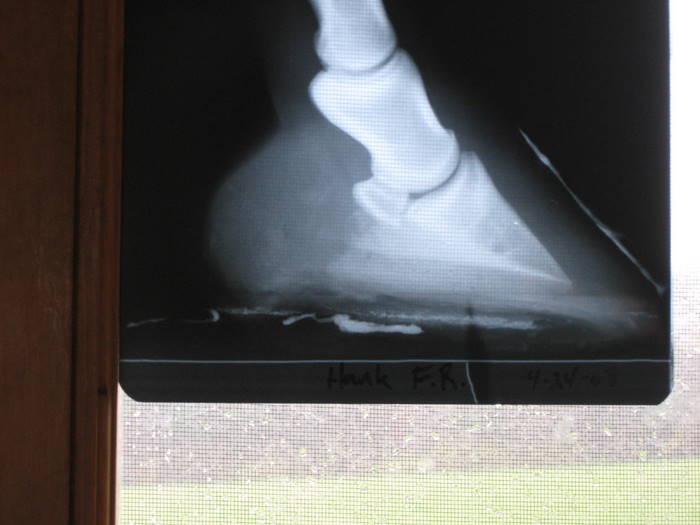

Here are his x-rays from 2007 a couple mos. after founder.

Here are x-rays from late April of this year

I don't know if that might help or not.

I agree with the comments about him looking like he's bearing too much weight on his sole. Also, looking at the x-rays, it looks like he may be somewhat out of balance and need more trimmed off one side, but I can't tell how the x-rays are labeled so am not sure which side. But, see how in the x-ray when looking at the bottom of the coffen bone you can see a shadow of the other side of the bone? (am I making myself clear?) The bottom of the bone should look straight across when the x-ray is taken from the side, with no shadow of the other side. A good way to tell about balance for sure is to get an x-ray that shows the two little holes where arteries go in the back of the hoof. (Sorry, I can't think what they are called.) If you go to https://www.horseadvice.com/horse/messages/21/15752.html there is an x-ray of the hoof and you can see these two "holes" above the blue line. On an x-ray you should be able to run a totally straight line between bisecting these two "holes." If you can, the horse is in balance laterally. This is according to a specialist (a vet who only deals with legs and feet)that I took one of our horses to.